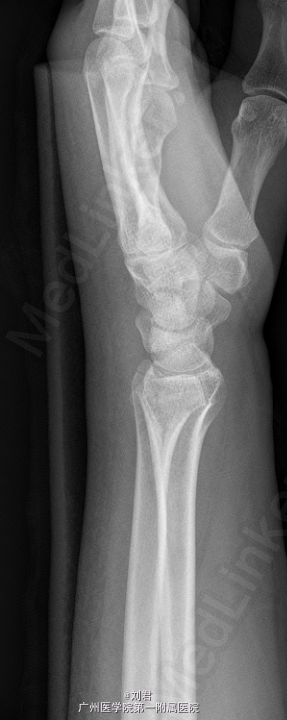

患者,女,51岁,因“摔伤致左腕肿痛伴活动障碍7天”入院。 患者7天前摔伤,左掌着地,致昨晚疼痛,疼痛为持续性,较剧,能忍,伴左腕活动障碍.

左腕石膏托固定,左腕肿胀,无明显畸形,压痛明显,左腕活动障碍,左手各指血运好,感觉正常,活动可。

初步诊断:1、 左桡骨远端骨折,2、左手第5掌骨软骨类肿瘤。在臂丛复合静脉麻醉下行“左掌骨内生软骨瘤切除术”,手术过程顺利,术后予以对症治疗。